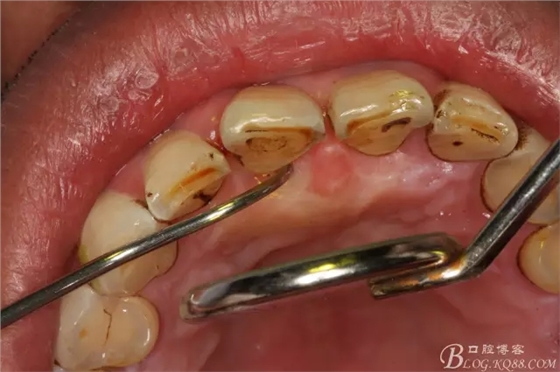

圖3.腭側(cè)牙周袋深約8mm.